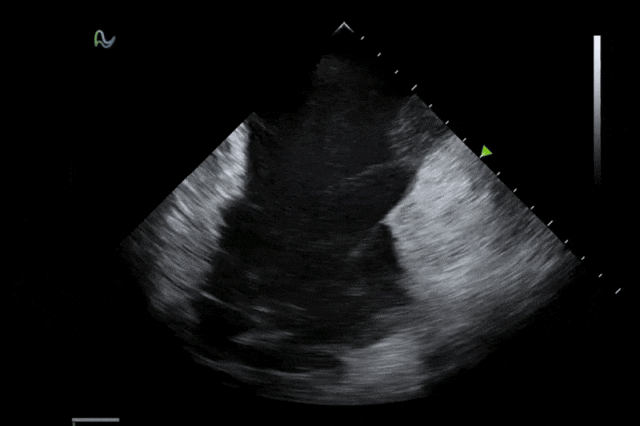

本次获批的ICE导管在全球首次采用了80阵元大孔径高密度探头设计,较传统普通的64阵元产品大幅度提升了成像分辨率、成像深度和图像对比度,可清晰辨识心脏细微结构和血流,为复杂手术给予更可靠的超声成像支持。同时,8F导管凭借更小的外径,显著提升导管顺利获得性和操控性,对病人创伤更小,尤其适合血管条件受限或小心脏患者;10F导管则凭借其优质的成像质量,为复杂心脏介入手术给予精准的影像引导。